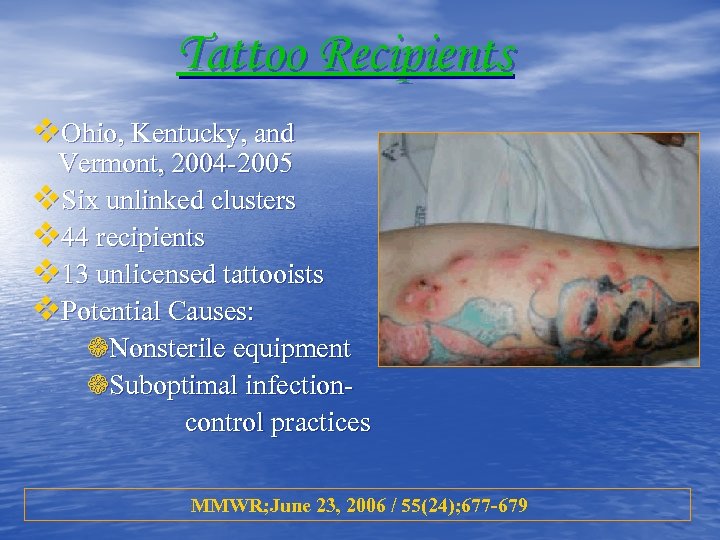

Tattoo Recipients v. Ohio, Kentucky, and Vermont, 2004 -2005 v. Six unlinked clusters v 44 recipients v 13 unlicensed tattooists v. Potential Causes: ❁Nonsterile equipment ❁Suboptimal infectioncontrol practices MMWR; June 23, 2006 / 55(24); 677 -679

Tattoo Recipients v. Ohio, Kentucky, and Vermont, 2004 -2005 v. Six unlinked clusters v 44 recipients v 13 unlicensed tattooists v. Potential Causes: ❁Nonsterile equipment ❁Suboptimal infectioncontrol practices MMWR; June 23, 2006 / 55(24); 677 -679